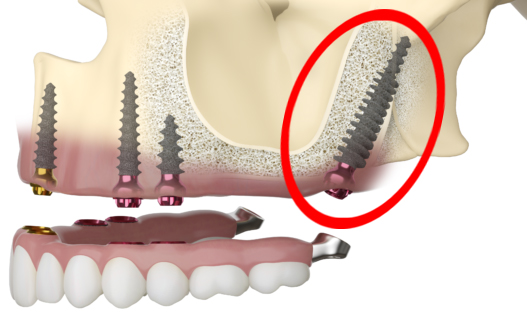

All On 4 Dental Implants

All On 4 dental implants offer a modern solution for individuals who have lost most or all of their teeth. This technique involves surgically placing four implants in the jaw, which act as anchors for a full arch of prosthetic teeth.

Unlike traditional implants, four implants are typically angled to enhance stability and make efficient use of the existing bone, often eliminating the need for bone grafting. This method is particularly beneficial for patients with significant bone loss who may not be candidates for conventional implants.

One of the most significant advantages of All On 4 dental implants is the possibility of immediate loading, allowing patients to receive a full set of temporary teeth on the same day as the surgery. This immediate functionality, combined with a high success rate and the potential for a lifelong tooth loss solution, makes All On 4 a popular choice.

Pterygoid Dental Implants

Pterygoid Dental Implants are the go-to choice for patients in need of comprehensive oral restoration who lack sufficient bone density in the upper jaw to support traditional implants.

Pterygoid Dental Implants represent an advanced option for complete oral rehabilitation in individuals who face the challenge of deficient bone volume in the upper jaw. These innovative implants derive their name from their unique placement in the pterygoid plate—a component of the sphenoid bone situated at the rear of the upper jaw.

One of the challenges with the All On 4 dental implant prosthetics is the cantilever effect, where the prosthetic teeth extend beyond the last implant, creating a lever that can lead to stress and potential failure. Pterygoid implants offer a solution to this cantilever issue by providing additional anchorage in the pterygoid plate, allowing for extended support without the drawbacks of a cantilever.

All On 4 Dental Implants

All On 4 dental implants offer a modern solution for individuals who have lost most or all of their teeth. This technique involves surgically placing four implants in the jaw, which act as anchors for a full arch of prosthetic teeth.

Unlike traditional implants, four implants are typically angled to enhance stability and make efficient use of the existing bone, often eliminating the need for bone grafting. This method is particularly beneficial for patients with significant bone loss who may not be candidates for conventional implants.

One of the most significant advantages of All On 4 dental implants is the possibility of immediate loading, allowing patients to receive a full set of temporary teeth on the same day as the surgery. This immediate functionality, combined with a high success rate and the potential for a lifelong tooth loss solution, makes All On 4 a popular choice.

Pterygoid Dental Implants

Pterygoid Dental Implants are the go-to choice for patients in need of comprehensive oral restoration who lack sufficient bone density in the upper jaw to support traditional implants.

Pterygoid Dental Implants represent an advanced option for complete oral rehabilitation in individuals who face the challenge of deficient bone volume in the upper jaw. These innovative implants derive their name from their unique placement in the pterygoid plate—a component of the sphenoid bone situated at the rear of the upper jaw.

One of the challenges with the All On 4 dental implant prosthetics is the cantilever effect, where the prosthetic teeth extend beyond the last implant, creating a lever that can lead to stress and potential failure. Pterygoid implants offer a solution to this cantilever issue by providing additional anchorage in the pterygoid plate, allowing for extended support without the drawbacks of a cantilever.